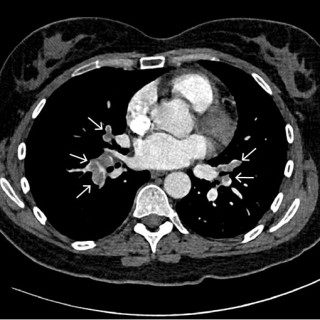

En mann i 50-årene ble innlagt etter residiverende episoder med brystsmerter. På innleggelsesdagen synkoperte han fra sittende stilling. Utredningsforløpet avdekket en diagnose som er sjelden, men med klassiske symptomer og funn. En mann i 50-årene med kjent hypertensjon, velregulert med kandesartan (tabletter, 8 mg × 1), ble henvist til akuttmottaket på grunn av episoder med brystsmerter. Han var normalvektig, hadde aldri røykt og hadde ingen rusbrukslidelse, og det var ingen kjent diabetes, hyperkolesterolemi, opphopning av hjertesykdom eller prematur hjertedød i familien. Over en periode på...